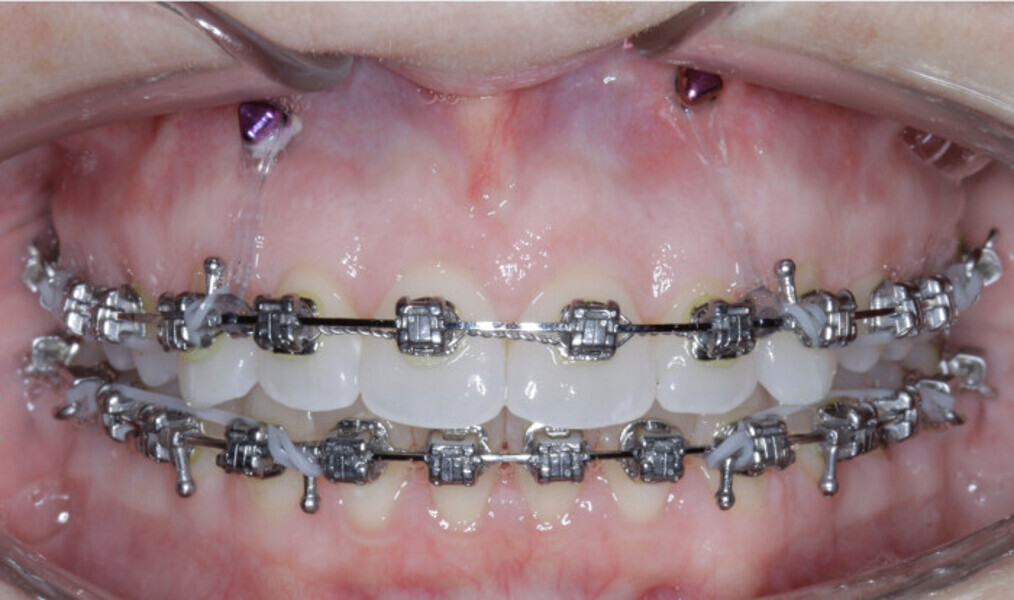

New Age orthodontics and orthopaedics with temporary anchorage devices